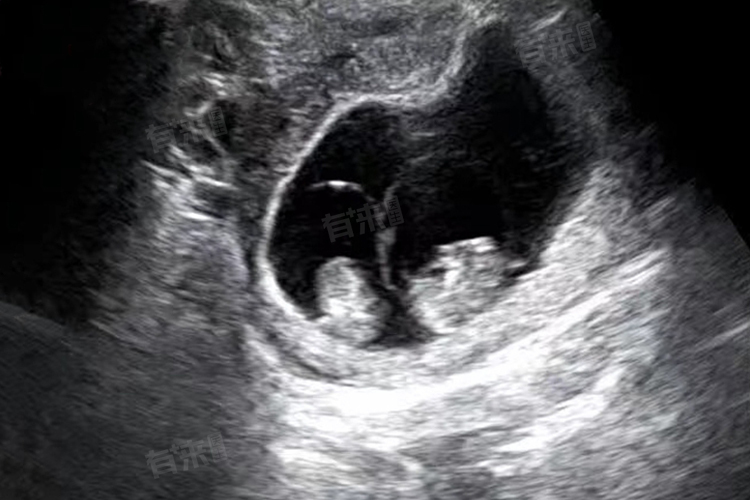

双胞胎,又称双胎妊娠,是指在B超检查时发现宫腔以内存在两个胎儿或两个孕囊的情况。尽管大多数情况下,每个孕囊内只会发育出一个胎儿,但在某些特殊情况下,一个孕囊中有可能包含两个胎儿,这被称为单卵双胞胎或同卵双胞胎。

值得注意的是,即使在一个孕囊中发现了两个胎儿,也不能立即断定就是双胞胎。还需要进一步的超声检查和观察来确认。同时,双胎妊娠相比单胎妊娠面临更大的风险,包括双胎输血综合征、选择性胎儿生长受限等并发症。因此,对于那些希望生育双胞胎的夫妇,应该在医生的指导下进行备孕和孕期管理,确保母婴的健康和安全。